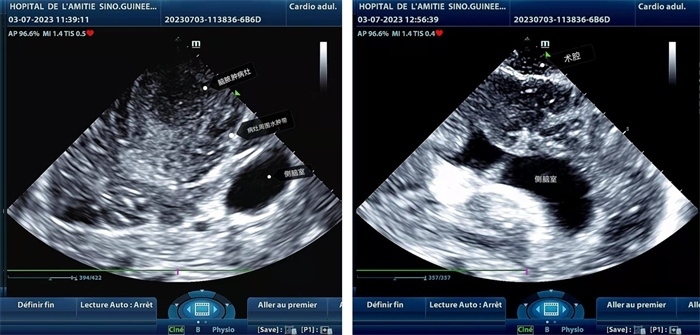

左圖顯示術(shù)中超聲見(jiàn)囊實(shí)性病變,大小約為4x4x3cm,病灶周圍腦組織水腫明顯;右圖為病灶切除后,術(shù)中超聲示術(shù)腔無(wú)病變殘留

左圖顯示術(shù)中超聲見(jiàn)囊實(shí)性病變,大小約為4x4x3cm,病灶周圍腦組織水腫明顯;右圖為病灶切除后,術(shù)中超聲示術(shù)腔無(wú)病變殘留。中國(guó)第二十九批援幾內(nèi)亞醫(yī)療隊(duì)供圖